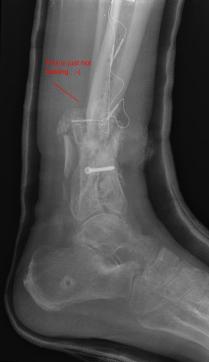

Post-skin graft & bone infuse surgery X-Rays of the left & right ankle

These x-rays were taken four weeks after surgery where grafts of skin were used to cover the open wound on Liam's left ankle. Dr. Gottlieb

infused bone material into the tibia gap of the left ankle. The 3 cm fragment in the left ankle does not appear to have fused or to be

obstructing normal movement so no immediate plans exist to modify the remaining bone fragments. Following these x-rays it is the plan to

remove the right ankle screw that was misplaced by Dr. Keller.